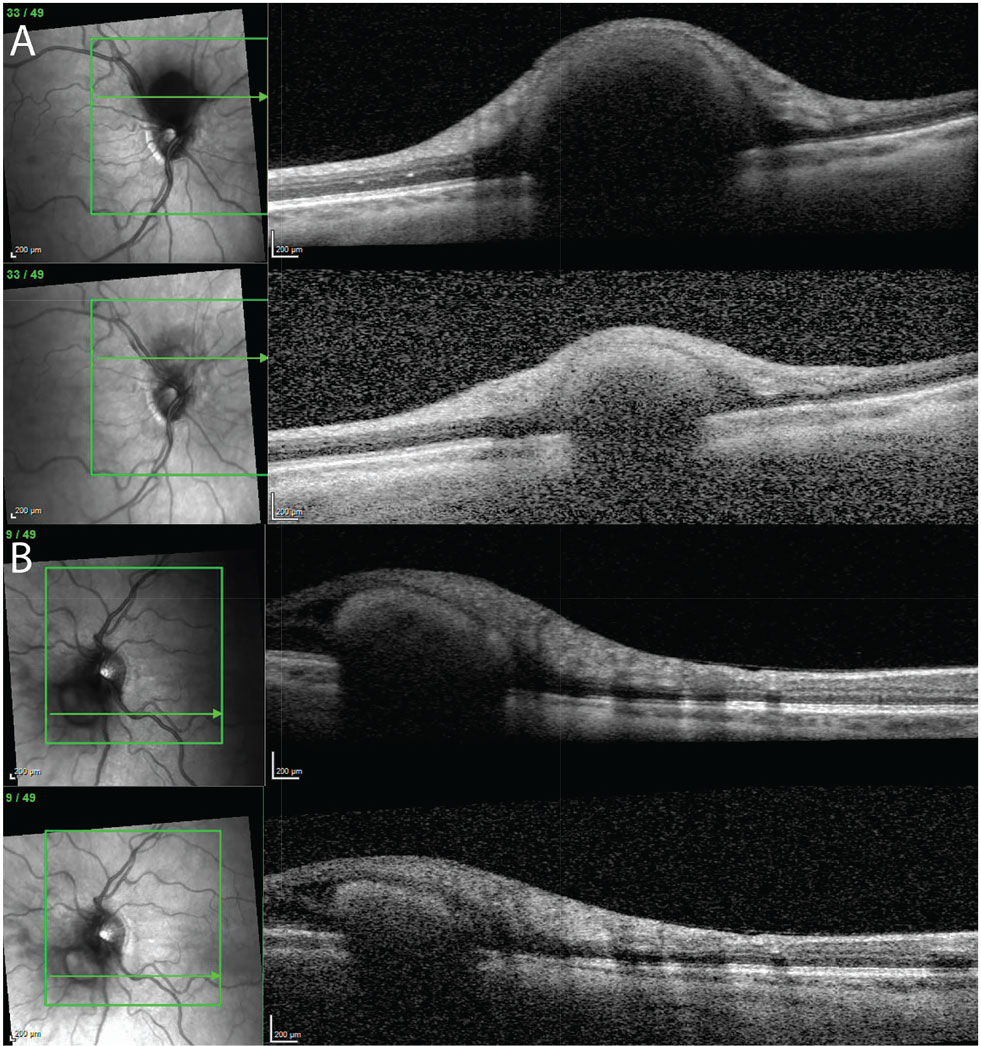

Figure 2. Optical coherence tomography imaging of the juxtapapillary tumors at baseline (top) and three months after initiating daily belzutifan treatment (bottom) in the (A) right and (B) left eyes. |

The patient followed up with the ophthalmology service three months after starting belzutifan. At follow-up, there was notable regression of the juxtapapillary tumors in both eyes (Figure 1 and Figure 2). She was tolerating the medication well.